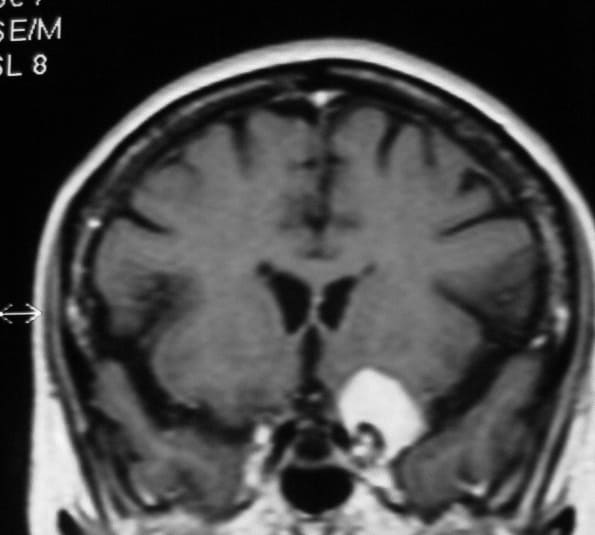

El diagnóstico se puede confirmar y el tumor localizar mediante:

• TAC cerebral

• RM cerebral